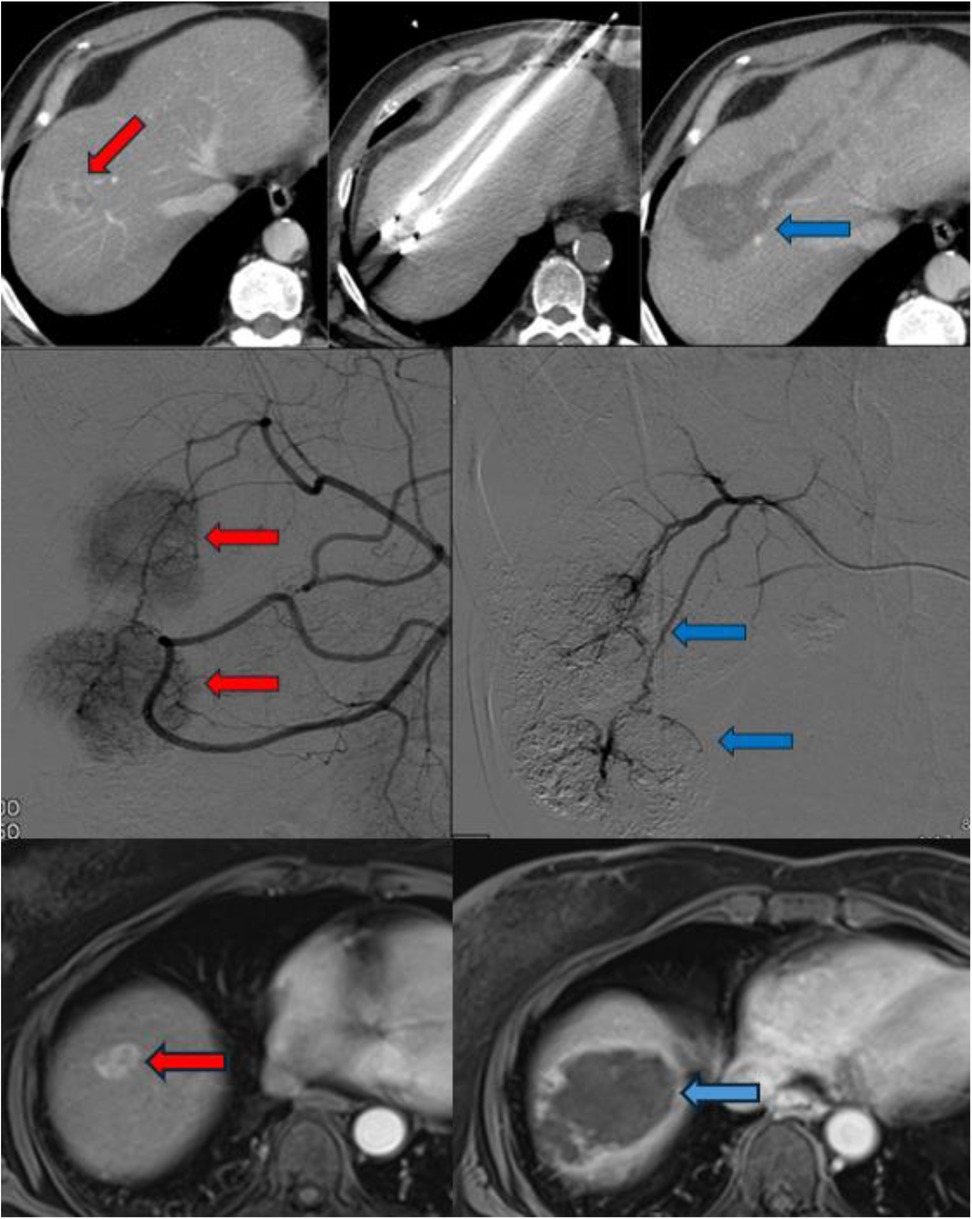

Technically similar to RFA, MWA has gained preference in cases where tumors are located near critical anatomical structures due to its ability to generate less heat diffusion (15). MWA rapidly heats tissues by inducing movement in water molecules, allowing for faster and higher temperatures (Figure 1). Unlike RFA, MWA causes less surrounding tissue damage and reduced inflammatory reactions, making it a safer option in sensitive locations.

Representative imaging of pretransplant locoregional therapies in HCC. Top row: Contrast-enhanced CT showing an enhancing HCC lesion (red arrow), ablation probe placement, and post-ablation cavity (blue arrow). Middle row: Digital subtraction angiography demonstrating tumor vascularity (red arrows) and post-TACE devascularization (blue arrows). Bottom row: MRI showing viable tumor with contrast uptake (red arrow) and post-TARE necrotic cavity (blue arrow).

Figure 1. The radiological imaging of patients who underwent MWA (upper column), TACE (middle column) and TARE (lower column). The red arrows indicate to HCC foci and the blue arrows indicate after procedures appearance.

Depending on the vascular anatomy, selective hepatic embolization targets the right or left hepatic arteries separately, while superselective embolization aims at smaller branches directly supplying the tumor (Figure 1). The choice of DEB size varies across studies, with smaller particles (100–300 µm or 300–500 µm) typically used first, followed by larger ones (500–700 µm) (16).

TARE, also referred to as radioembolization, y90 or selective internal radiation therapy (SIRT), involves the selective intra-arterial administration of microspheres loaded with radioactive compounds—most commonly Yttrium-90 (^90Y) or Lipiodol labeled with Iodine-131 (^131I) or Rhenium-188 (^188Re)—via percutaneous access. Among these, Yttrium-90 has become the most widely used radionuclide. It is a pure β-emitter, characterized by a short half-life (64.2 h) and limited tissue penetration (average 2.5 mm, maximum 11 mm) (24). Deployment devices aid in the administration of Y90 directly into the tumor minimizing contamination to non-targeted areas (Figure 1).